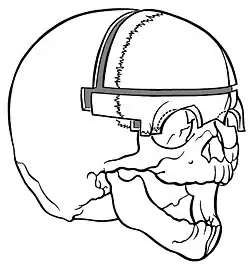

Fronto-supraorbital advancement and remodelling

A form of surgery is the so-called fronto-supraorbital advancement and remodelling.[33] Firstly, the supraorbital bar is remodelled by a wired greenstick fracture to straighten it. Secondly, the supraorbital bar is moved 2 cm. forward and fixed only to the frontal process of the zygoma without fixation to the cranium. Lastly, the frontal bone is divided into two, rotated and attached to the supraorbital bar causing a nude area (craniectomy) between the parietal bone and frontal bone. Bone will eventually regenerate since the dura mater lies underneath (the dura mater has osteogenic capabilities). This results in an advancement and straightening of the forehead.

'Floating forehead technique'

The so-called 'floating forehead technique'[2] combined with the remodelling of the supraorbital bar is derived from the fronto-supraorbital advancement and remodelling. The supraorbital bar is remodelled as described above.[34][35] The frontal bone is split in two pieces. Instead of using both pieces as in fronto-supraorbital advancement and remodelling, only one piece is rotated and attached to the supraorbital bar. This technique also leaves a craniectomy behind.[36]